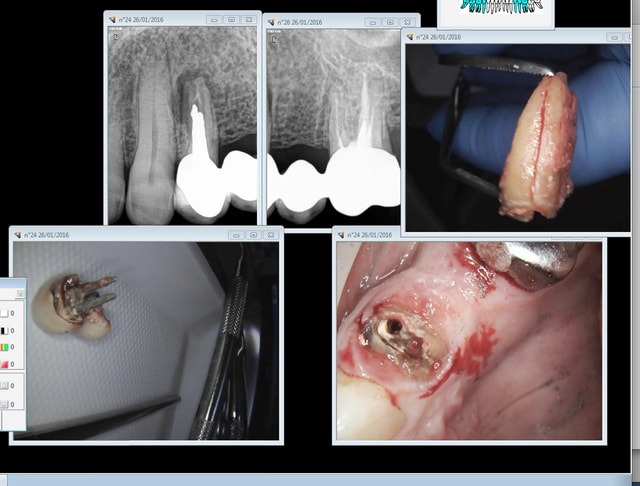

Algi tu fais quoi quand on est arrivé au bout du bout de la solvabilisation ?

Cas concret quand on a "solvabilisé " morceau par morceau pendant des années le gentil dentiste va devenir méchant. -)))

Pas mal les bridges hein ? et une et deux et 3 -0. Strike ! Allo ? Houston ? on a un problème ! )-)))

Je pense qu'il va falloir "bridger" jusqu'à la 21 ( histoire de ratisser un max de prestations sécu et mutuelle et rester gentil lol !)) , on a le droit de bousiller 13 mais quid de 22 et 21 pour les besoins du service ?

Autre problème potentiel : 26 va elle tenir la distance ? -)

Capture d e cran 2016 01 26 14.02 - Eugenol